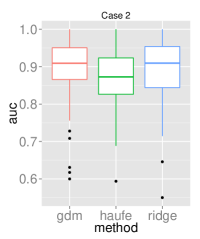

Multi-site study

To assess the predictive performance of the compared methods in a multi-site setting, we used the Schizophrenia dataset that comprises data from three sites. All models had their respective parameters cross-validated while training in one site before making predictions in the other two sites. Each training involved using of the site samples to allow for resampling the training sets 100 times to yield a distribution. The reproducibility across the resampled sets was measured using the inner product between model parameters. The multi-site prediction and reproducibility results are visualized in figure 3.

In five out of six cross-site prediction settings, GDM outperformed all compared methods in terms accuracy. Also, GDM had higher reproducibility than ridge regression, while having slightly lower reproducibility than the generative procedure in Haufe et al. (2014).